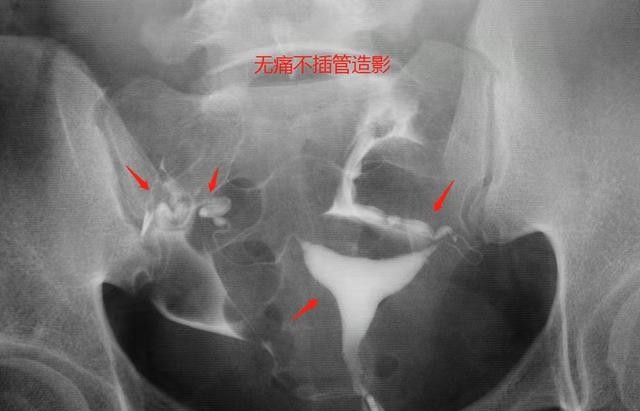

输卵管造影检查完成后,个人想知道其结果是否正常其实很简单,如果片子的正常的,那么能够明显看到造影剂涂抹了整个输卵管;如果存在输卵管堵塞的问题,那么造影剂就会不显..

看懂输卵管造影片子只需一分钟,正常或异常影像表现不一样